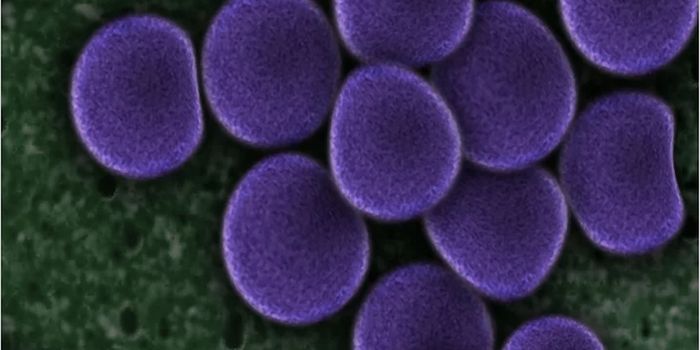

SEP 17, 2021Cell & Molecular BiologyMRSA (methicillin-resistant Staphylococcus aureus) is a well known superbug, a pathogenic microbe that can cause serious ...